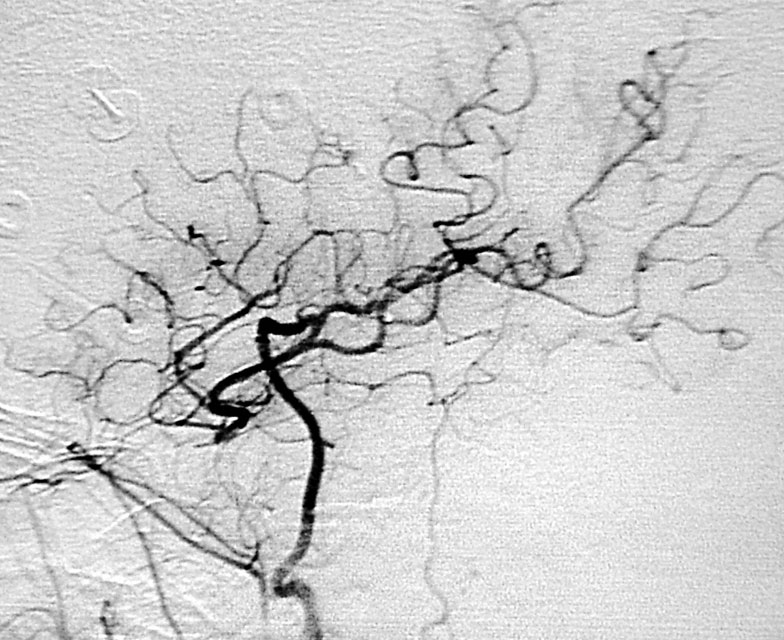

脳動静脈奇形は先天性の血管奇形のひとつで脳出血や痙攣発作の原因となります。最も基本的な治療法は手術による全摘出ですが、大きさ、発生場所等によっては放射線治療が選択される場合もあります。

当科では放射線治療班と症例検討を行い、個々の患者さんに最も適切は治療を提供しています。 脳動静脈奇形の手術では、術中脳血管撮影を常に行い、全摘出を確認しています。また場合によっては脳動脈瘤手術同様に電気生理学的モニタリングも併用し、確実、安全な手術を行っています(図7、8)。